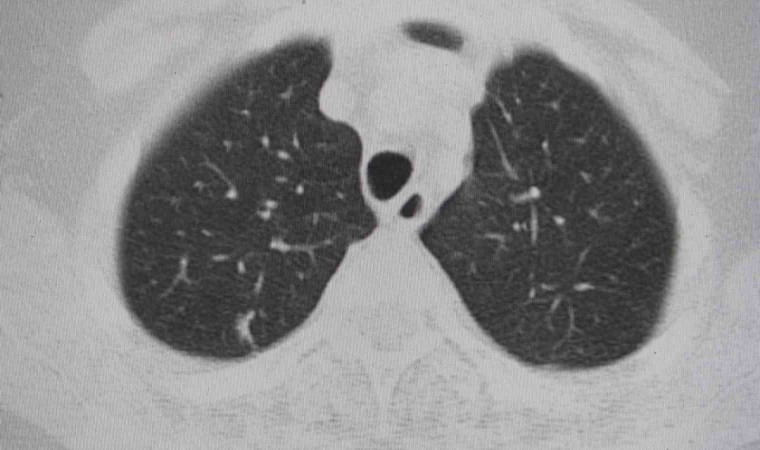

Doç. Dr. Onur Ermerak, "Akciğer kanseri, dünyada kanser nedenli ölümlerde en sık rastlanan ölüm nedenidir. Akciğer kanserinde henüz tarama aşamasına gelemedik. Amacımız o aşamaya gelip erken evrede akciğer kanserini yakalayıp o hastalığı tedavi etmeye başlamaktır. Akciğer kanserinin sigarayla ilişkili olduğunu biliyoruz. Çevre kirliliği, çeşitli kimyasallar akciğer kanserine neden olmaktadır. Maalesef geç bulgu ve şikayet verdiği için hastalar genelde geç evrede yakalanıp tedaviden yarar göremeyecek durumda bize başvuruyorlar. Sadece yüzde 15 hastada sağ kalım görülmektedir. Biz onu çok daha yüksek rakamlara çıkartıp hastalarımıza güzel günler sunmak istiyoruz. Öksürük, istenmeyen kilo kaybı, kanlı balgam, halsizlik, yorgunluk ve iştah kaybı gibi etkilerle görülmektedir. Özellikle kilo kaybı ve geçmeyen öksürük bizim için çok önemli bir bulgudur. Bu hastaların bize başvurmaları gerekir. Burada altını çizmek istediğimiz nokta, tarama programlarıyla sağ kalımda da yüzde 40’lara kadar bir artış sağlamaktayız. Tarama programı, düşük doz tomografilerle hastaları tarayıp bu hastalık daha oluşma aşamasındayken en güzel tedaviyi verip hastaların akciğer kanseri ile baş başa kalmamasını sağlıyoruz. 50 yaş üstünü geçmiş ve 15 yıl sigara tüketmiş hastaların hepsi tarama yapmalıdır. Bizim ülkemizde de aktif sigara kullanımının yanında pasif içicilik de devam ediyor ve biz bu konuyu ciddiye almalıyız. Akciğer kanserine yakalanan hastaların yüzde 90’ı sigara içmekte. Bunların arasında da yüzde 50’si sigarayı bırakmış hastalar oluyor. Hastaların merkezlere başvurup taramasını yapıp hastalığı erken evrede yakaladıktan sonra en uygun tedavilerle sağlığına kavuşmasını amaçlamaktayız. Sigara içmemek çok önemli. Sigara içilen ortamda dahi bulunmamaları çok önemli. Ve farkındalığı oluşturup en ufak bir şüphede gerekli tarama endikasyonlarıyla gidip taranmalarını öneriyoruz. Akciğer kanseri sinsi bir kanserdir, geç bulgu ve şikayet veriyor. Öncelikle sigara içmeyelim ve hastalığın taramasını mutlaka yaptıralım" dedi.